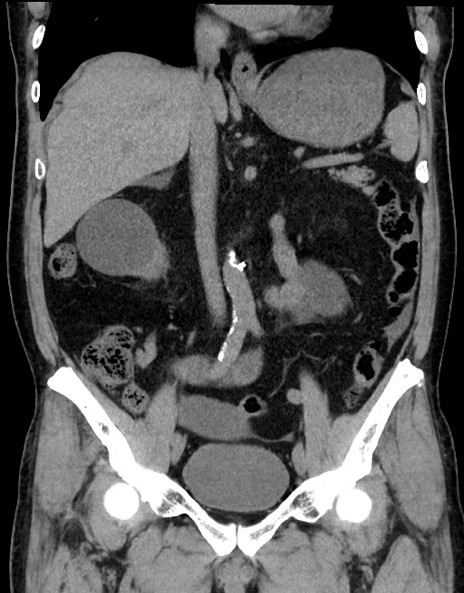

症例15(冠状断像)

【症例】70歳代男性

【主訴】腹痛

【現病歴】今朝から腹痛あり。全体的に痛い。特に左上の方。排ガスが今日はない。冷や汗が出る。

【既往歴】直腸癌術後

【身体所見】左側腹部〜上腹部に圧痛あり。腹膜刺激症状明らかなではない。軽度反跳痛。左下腹部に術後瘢痕あり。

【データ】WBC 7700、CRP 0.02